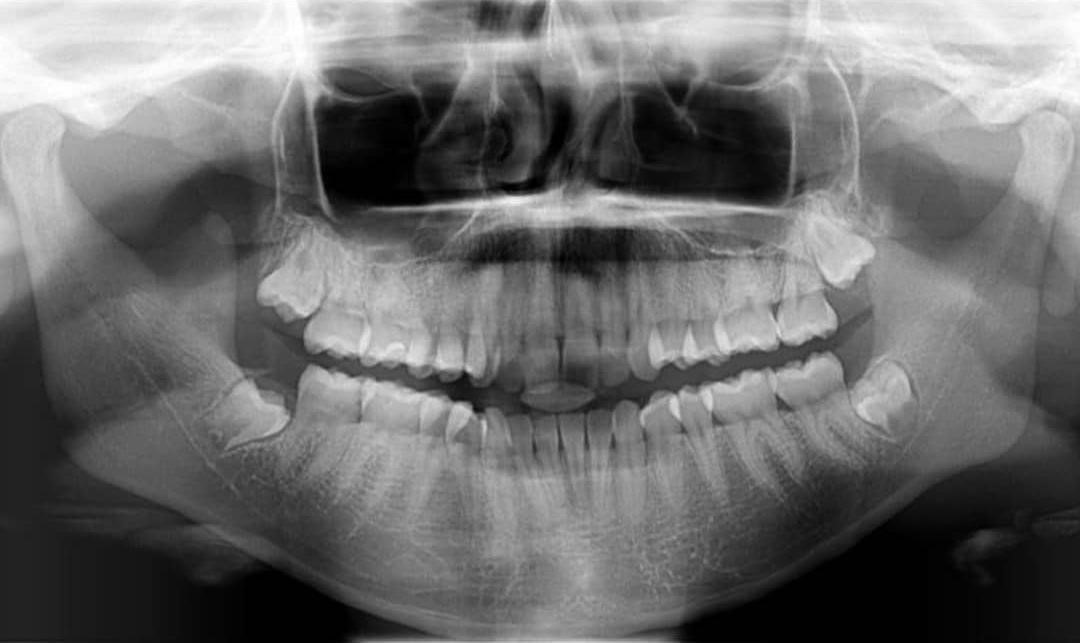

Caso 1